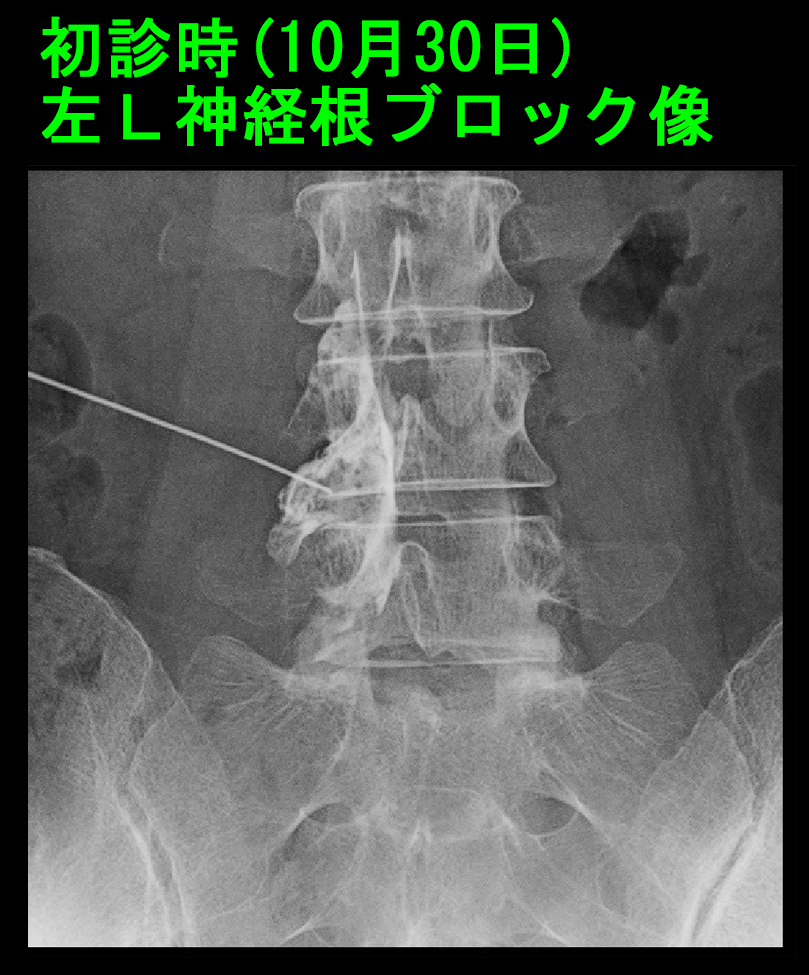

元々MRI画像の水平断ではL45での脊髄は逆三角形となっていて、最も脊髄の圧迫の強い高位だったのですが、椎間板ヘルニアは右側で優位であるため、左坐骨神経痛を訴えるYさんの病因ではないであろうと除外していました(赤矢印)。でもYさんの病因はL34でもL5Sでもありませんでした。L23の水平断の圧迫はごく軽微ですし、これも右優位です。L34でもL5Sでもなければ、L45しかないと判断しました。同日、右L5神経根ブロックを施行しました。

54才女 Xp4.jpg